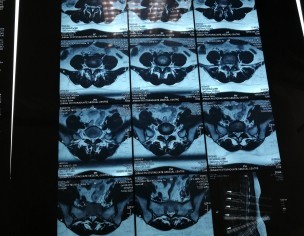

Attaching my MRI reports (MRI was in July). Everyone told me there is nothing serious just go for painkillers and physiotherapy. I was taking naproxen and was on physiotherapy from last 2 months. But still, there is no improvement. Sometimes I face severe back pain. So can someone please guide me what to do now? Please don't suggest me any treatment which is expensive as already invested a lot but all in vain. Is this disc herniation? Is it curable? I am seriously worried about it.

Cant attach my MRI report as there is no Attach option

Attach Photo here: